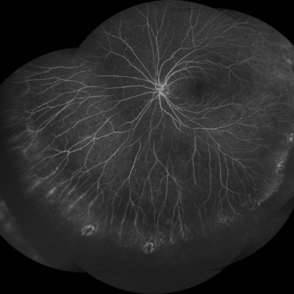

FEVR

Nov 22 2022 by Vaidehi Sathaye

Widefield FA montage of LE of a 23 year old male patient with FEVR

Photographer: Dr. Vaidehi Sathaye

Imaging device: Mirante

Condition/keywords: FA, familial exudative vitreoretinopathy (FEVR)